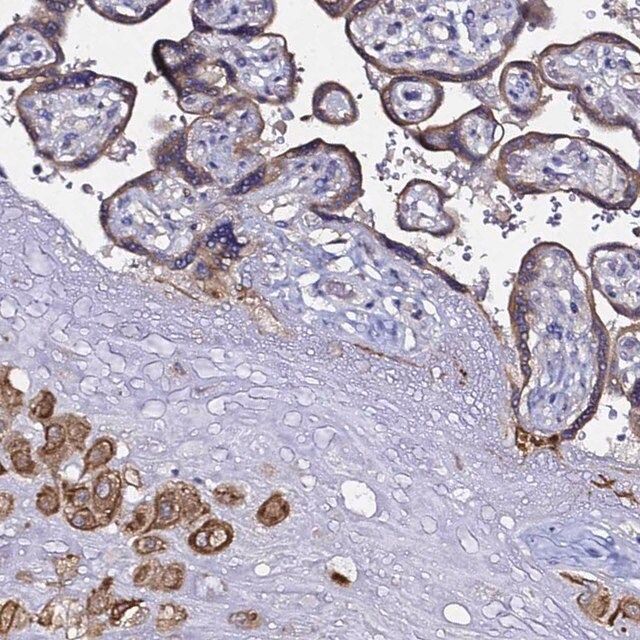

The Human Protein Atlas project can be subdivided into three efforts: Human Tissue Atlas, Cancer Atlas, and Human Cell Atlas. The antibodies that have been generated in support of the Tissue and Cancer Atlas projects have been tested by immunohistochemistry against hundreds of normal and disease tissues and through the recent efforts of the Human Cell Atlas project, many have been characterized by immunofluorescence to map the human proteome not only at the tissue level but now at the subcellular level. These images and the collection of this vast data set can be viewed on the Human Protein Atlas (HPA) site by clicking on the Image Gallery link. To view these protocols and other useful information about Prestige Antibodies and the HPA, visit sigma.com/prestige.

- IHC tissue array of 44 normal human tissues and 20 of the most common cancer type tissues.